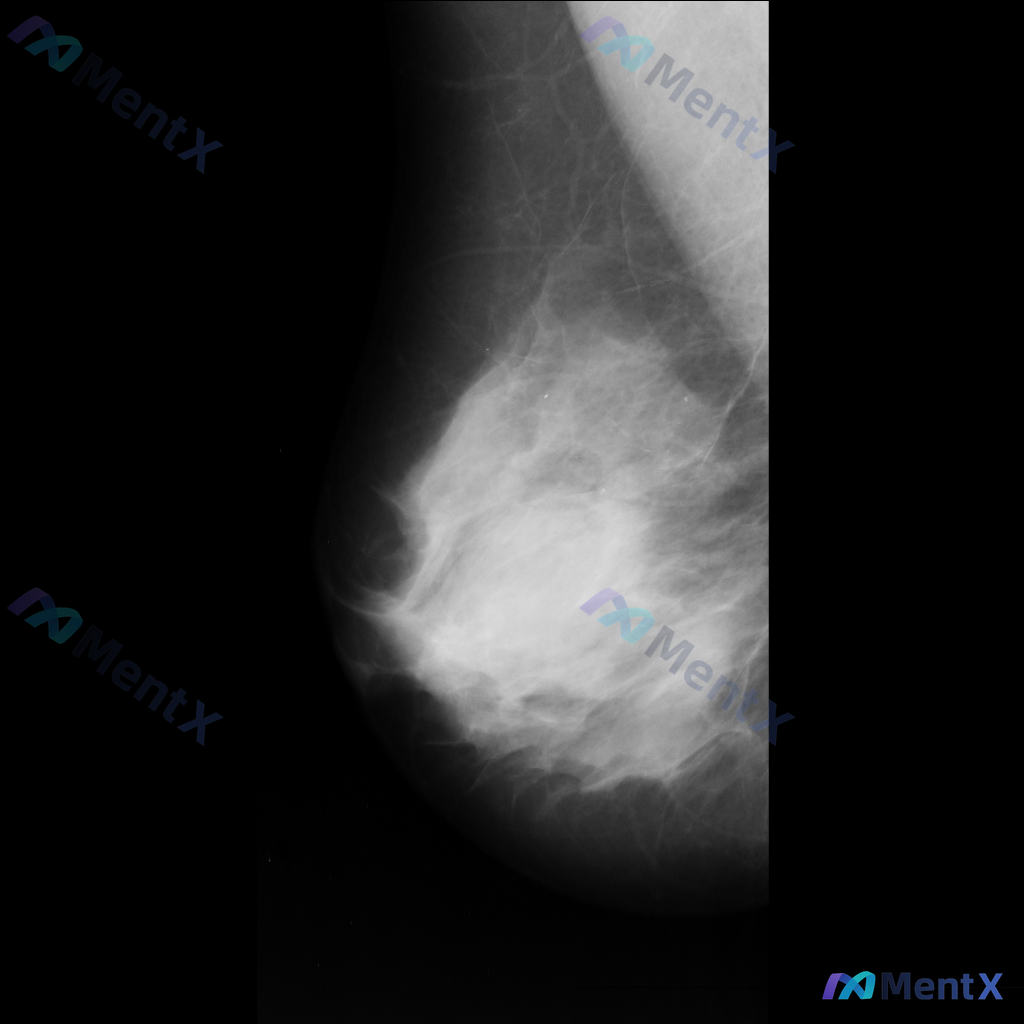

这张乳腺钼靶片的异常表现,你会先往哪个方向考虑?

影像可见:不规则、高密度肿块/不对称致密影,伴有毛刺状边缘、结构扭曲和散在钙化。

目前考虑可能存在几种不同的异常方向,想先听听大家的第一反应——单看这组影像特征,你会先往哪种情况考虑?